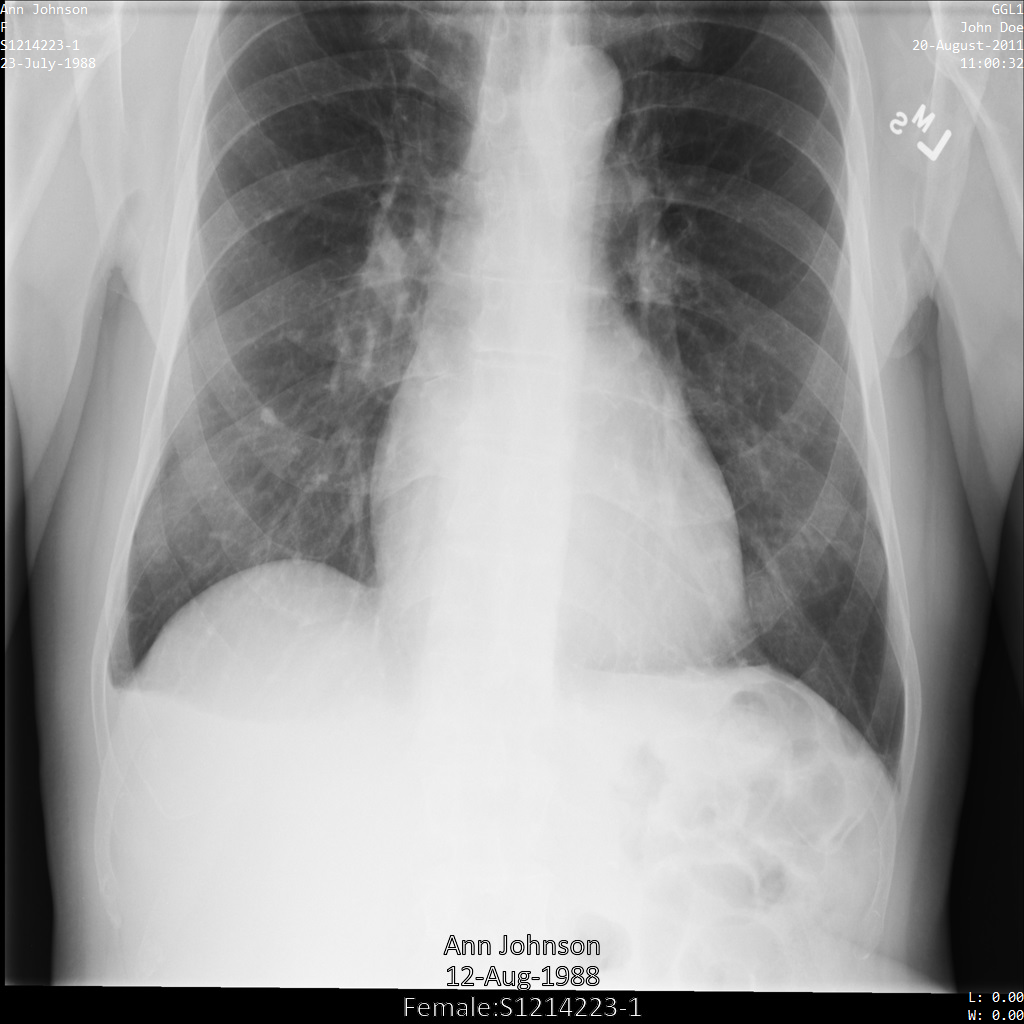

将图片提交到 Cloud Healthcare API 后,图片显示如下。除了 removelist 中提供的标记之外,便只有 PatientBirthDate 会从图片中移除,因为它是 removelist 中唯一与图片中可见的元数据对应的标记。

虽然图片顶部角落的 PatientBirthDate 已根据 removelist 中的配置进行了遮盖,但图片底部的烧屏 PHI 仍会保留。如需一并移除烧屏文字,请参阅遮盖图片中的烧屏文字

dicom_removelist